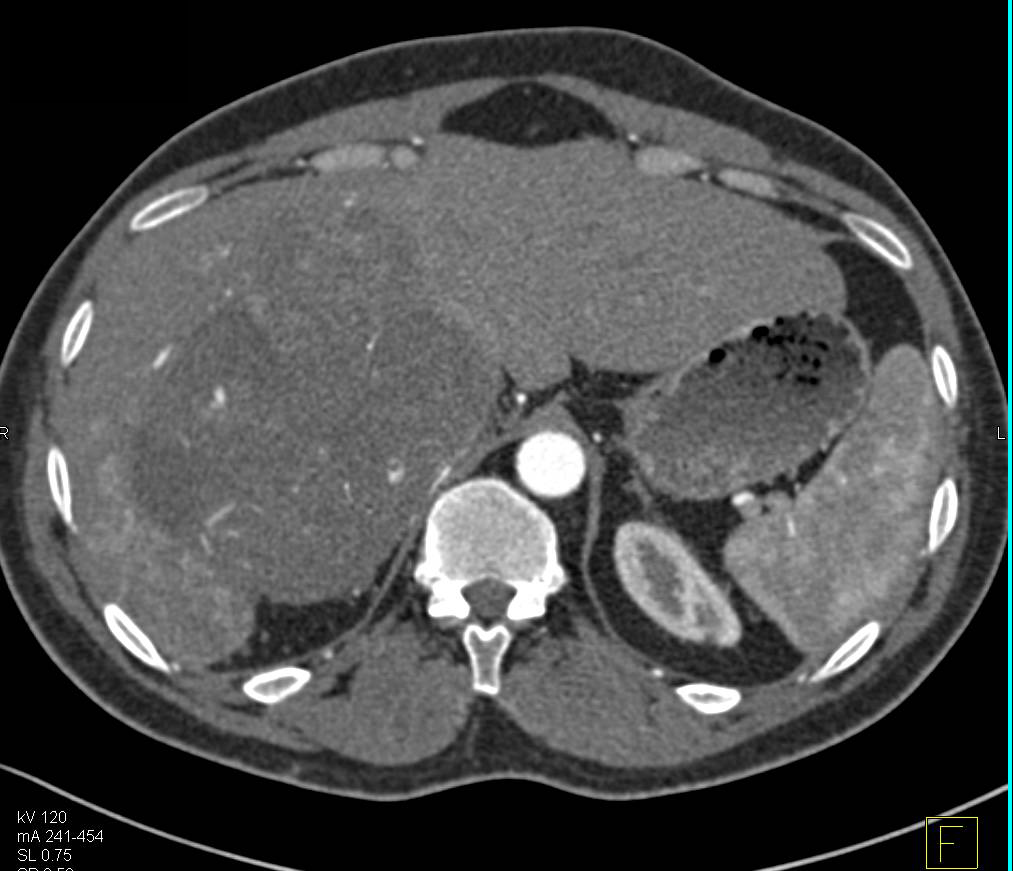

Cholangiocarcinoma with Stent and Bulky Nodes in Porta Hepatitis